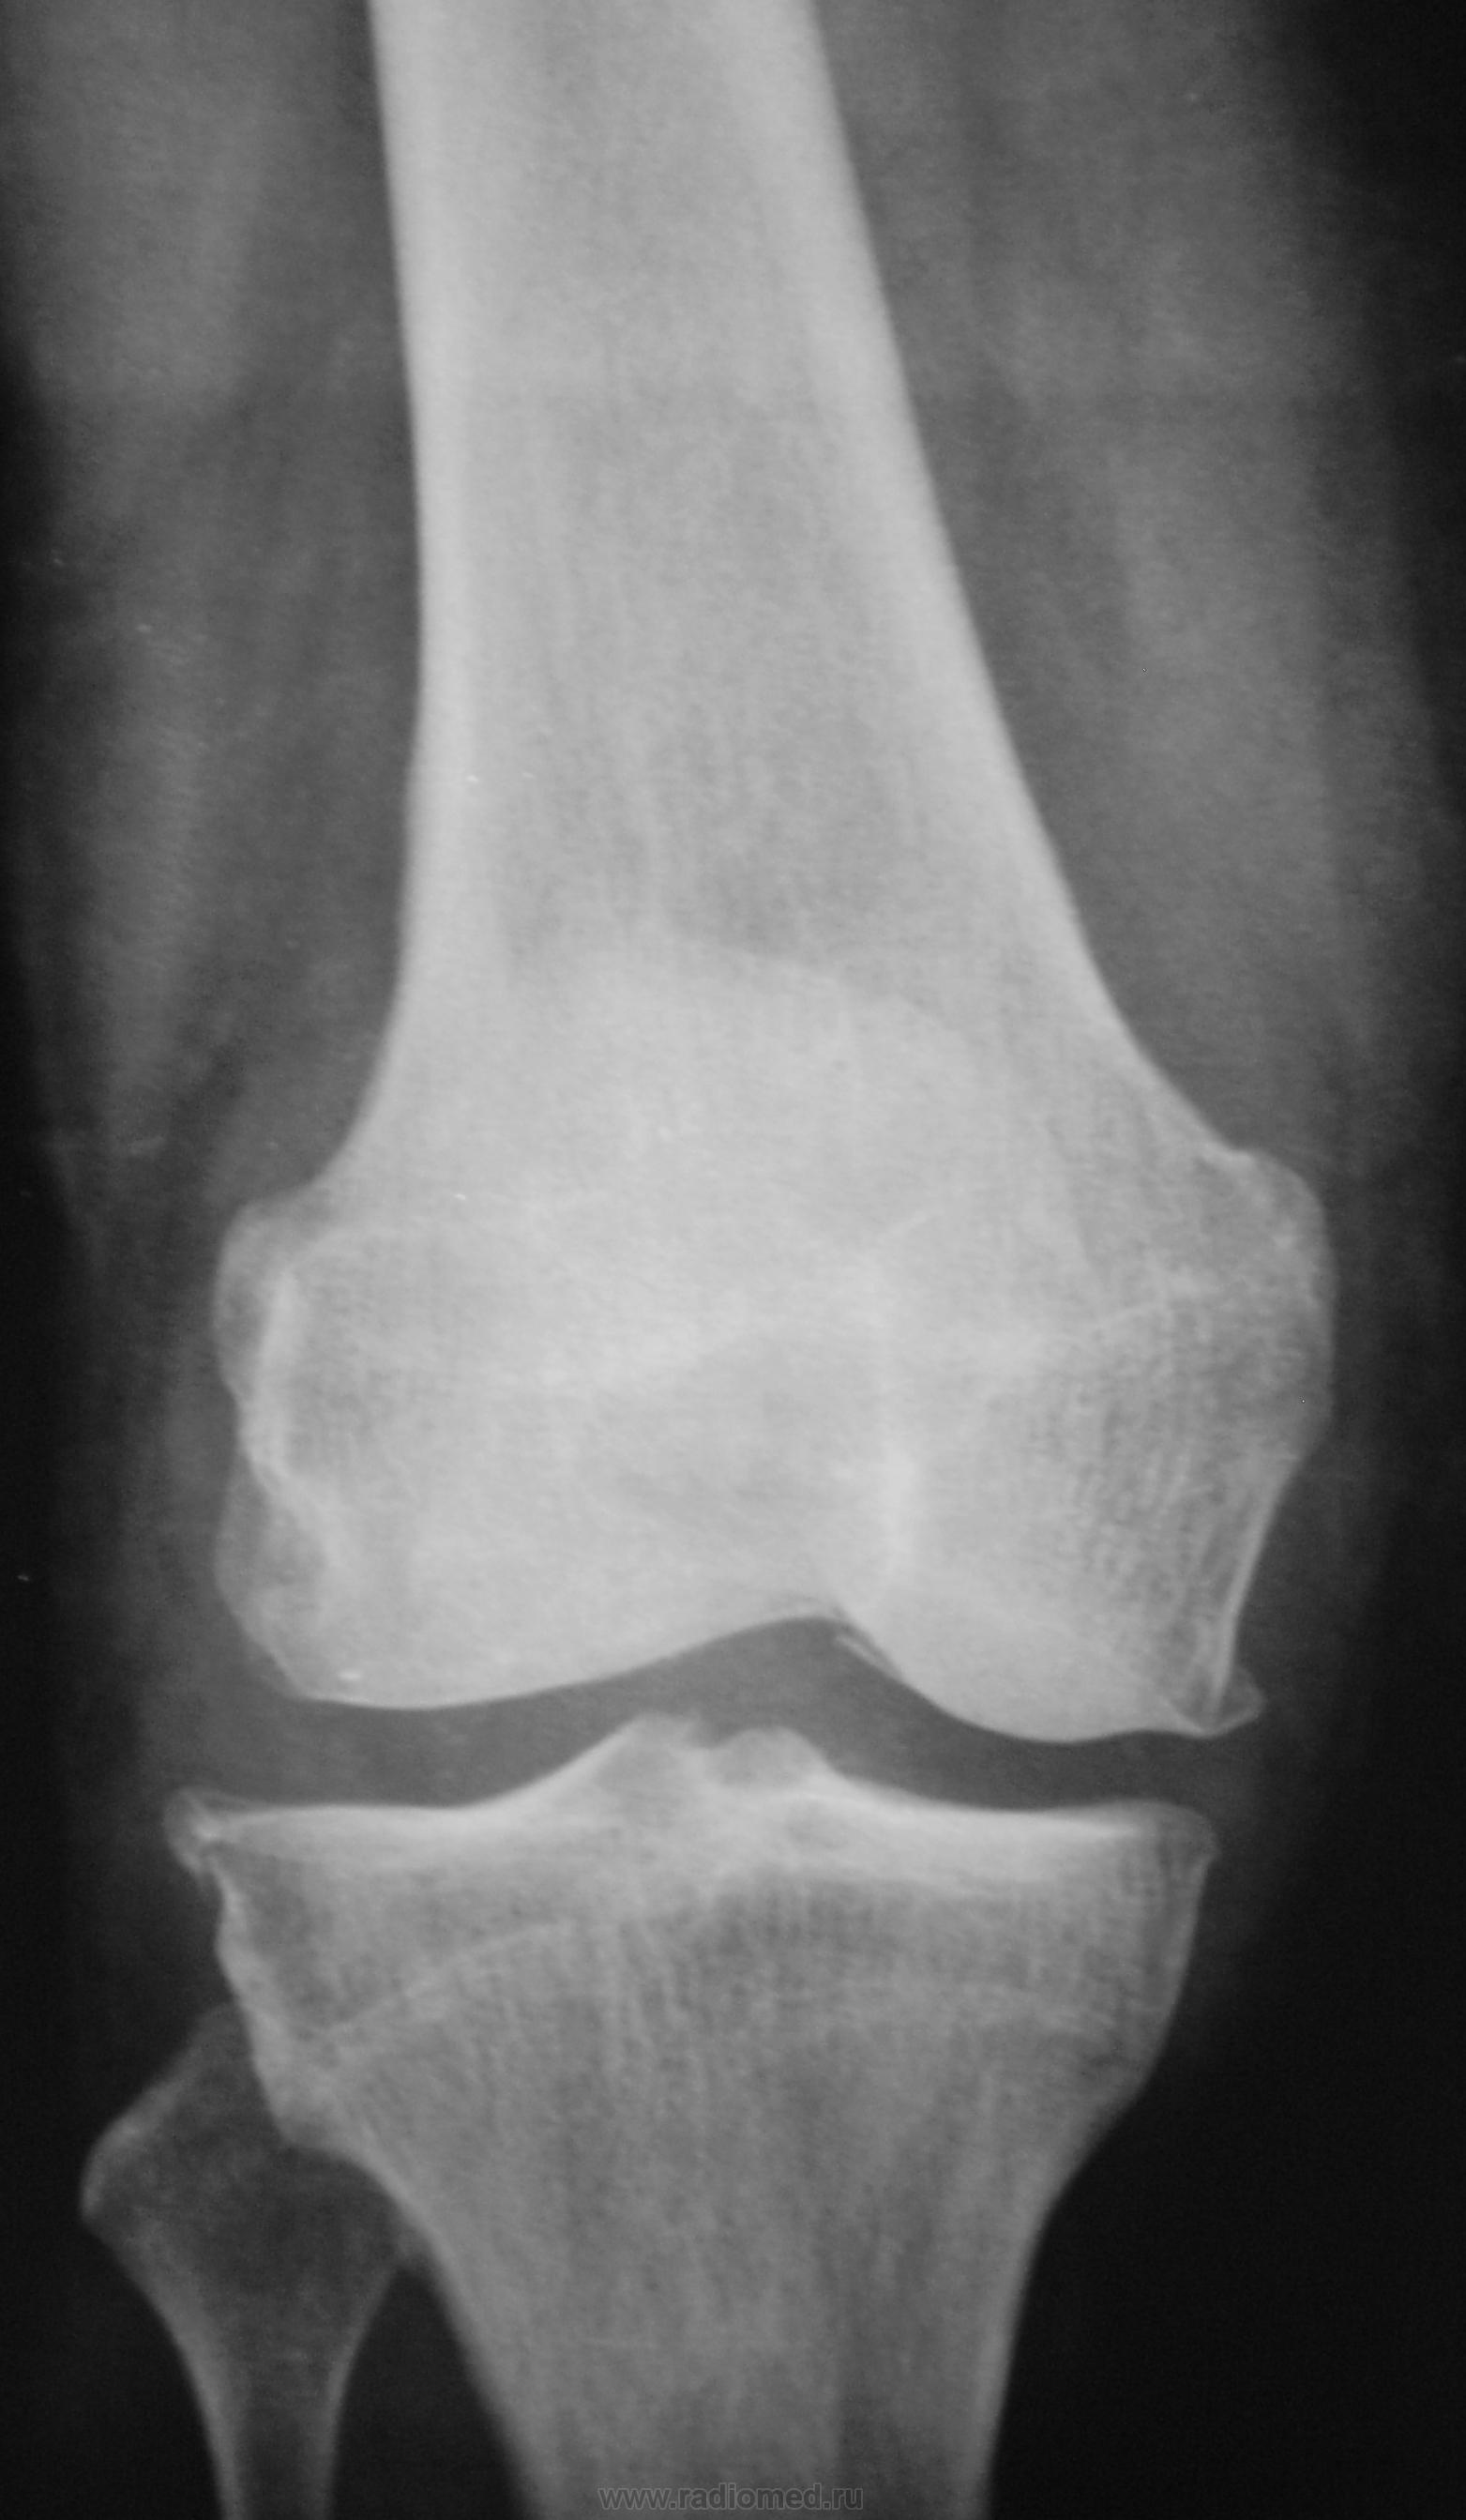

С диагнозом ДОА, пациент направлен на рентгенографю коленного сустава.

Деформирующий артроз. Есть признаки обызвествления мест прикрепления крестообразных связок, собственной связки надколенника.

Щель уж больно широка для такого артроза. Может там на фоне артроза какой-нибудь реактивный артрит?

Артрит (R) = периартикулярный остеопороз.

ДОА коленного 2 ст. и надколенно-большеберцового сустава 3-4 стадий (по Larsen)..